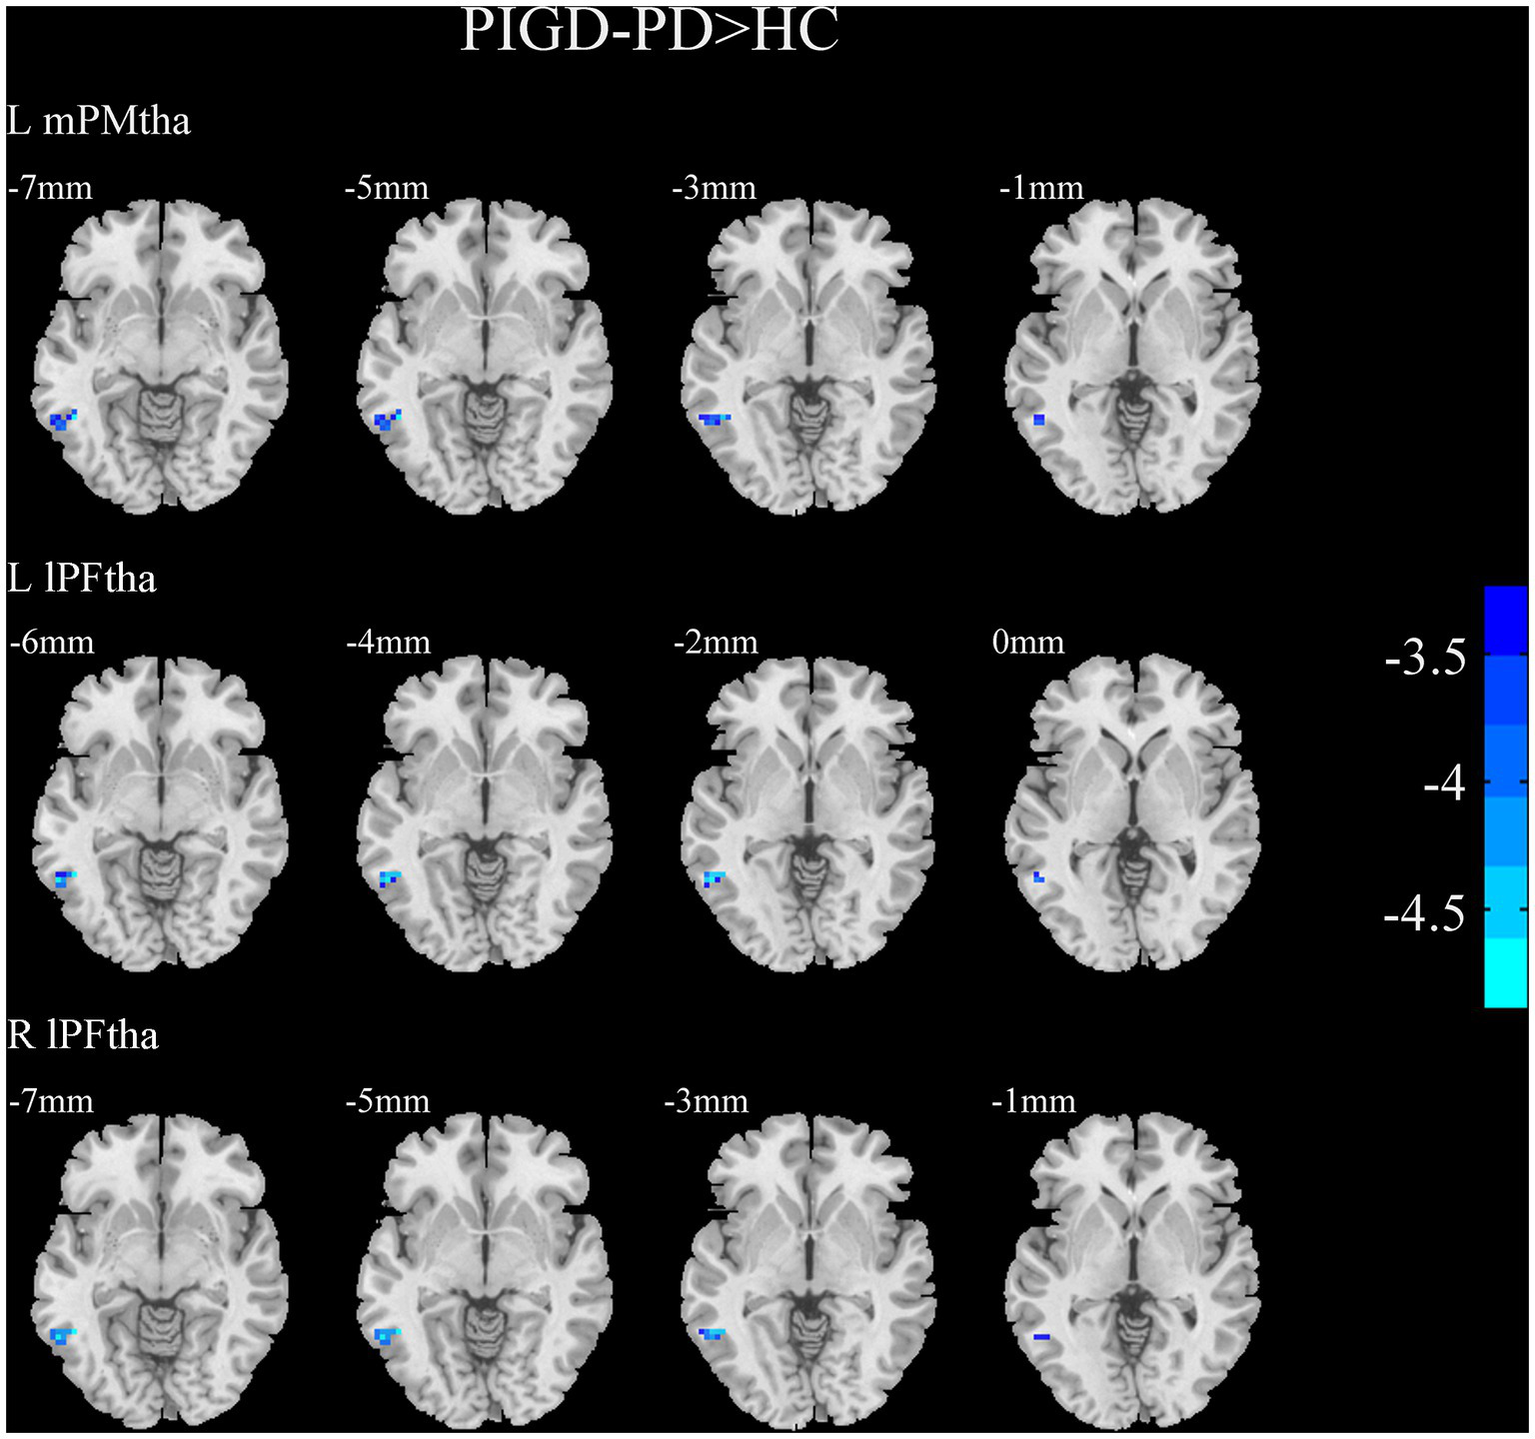

A two-sample t-test of the differences between the TD and PIGD patients showed that the TD group had higher FC between the right mPFtha, bilateral mPMtha, left Stha, bilateral lPFtha, and the left MTG; between the left Stha and the right SFGdl; and between the right Otha and the left MOG, as well as the right STG (Figure 3). The FC between left Stha and the right SFGdl and between the right Otha and the left MOG in the TD group was higher than that in the HC group (Figure 4). The PIGD group had lower FC between the left MTG and the left mPMtha, as well as bilateral lPFtha than the HC group (Figure 5).

Figure 5

Results of two-sample t-test between PIGD patients and HCs. All results are in MNI space, the red color represents the increased FC, while the blue color represents the decreased FC (voxelwise threshold of p < 0.001 combined with a GRF-corrected clusterwise threshold of p < 0.05).